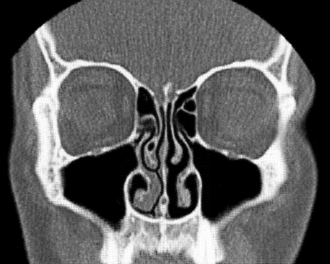

Anatomisch gehört die Nase zu den äußeren und oberen Atemwegen. Die Nasenlöcher (Nares) führen in das Innere der Nase, jeweils zuerst in den Nasenvorhof (Vestibulum nasi), der von behaarter äußerer Haut ausgekleidet ist, dann in die eigentliche Nasenhöhle (Cavum nasi). Die Nasenhöhle ist durch die Nasenscheidewand (Septum nasi) in zwei getrennte Abteilungen gegliedert und von einer Schleimhaut mit Flimmerepithel ausgekleidet. Linke und rechte Nasenhöhle sind jeweils durch die knöchern gestützten Nasenmuscheln (Conchae nasales) untergliedert. Zwischen den Nasenmuscheln liegen drei Nasengänge (Meatus nasi).